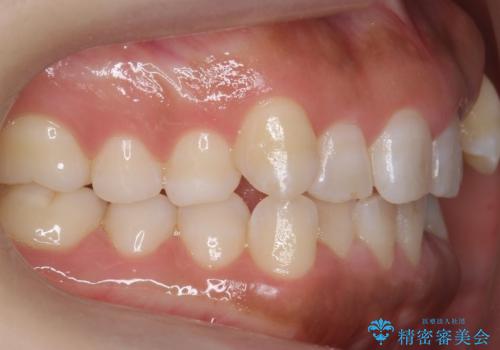

八重歯を非抜歯で マウスピースで治療 奥歯を後ろに下げてすき間を確保

奥歯を後ろに下げてすき間を確保し、八重歯を引っ込めて並べる治療を行いました。

かなり真面目に使っていただいた印象で、綺麗に動きました。

装着時間や、チューイーの使用頻度を含む協力度もかなり治療の成否に関係があります。